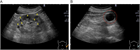

1. 片側の腰背部痛や側腹部痛では水腎症を念頭に置き、まず超音波検査を行い、尿路閉塞の位置と原因を同定するには単純CTを撮影する。